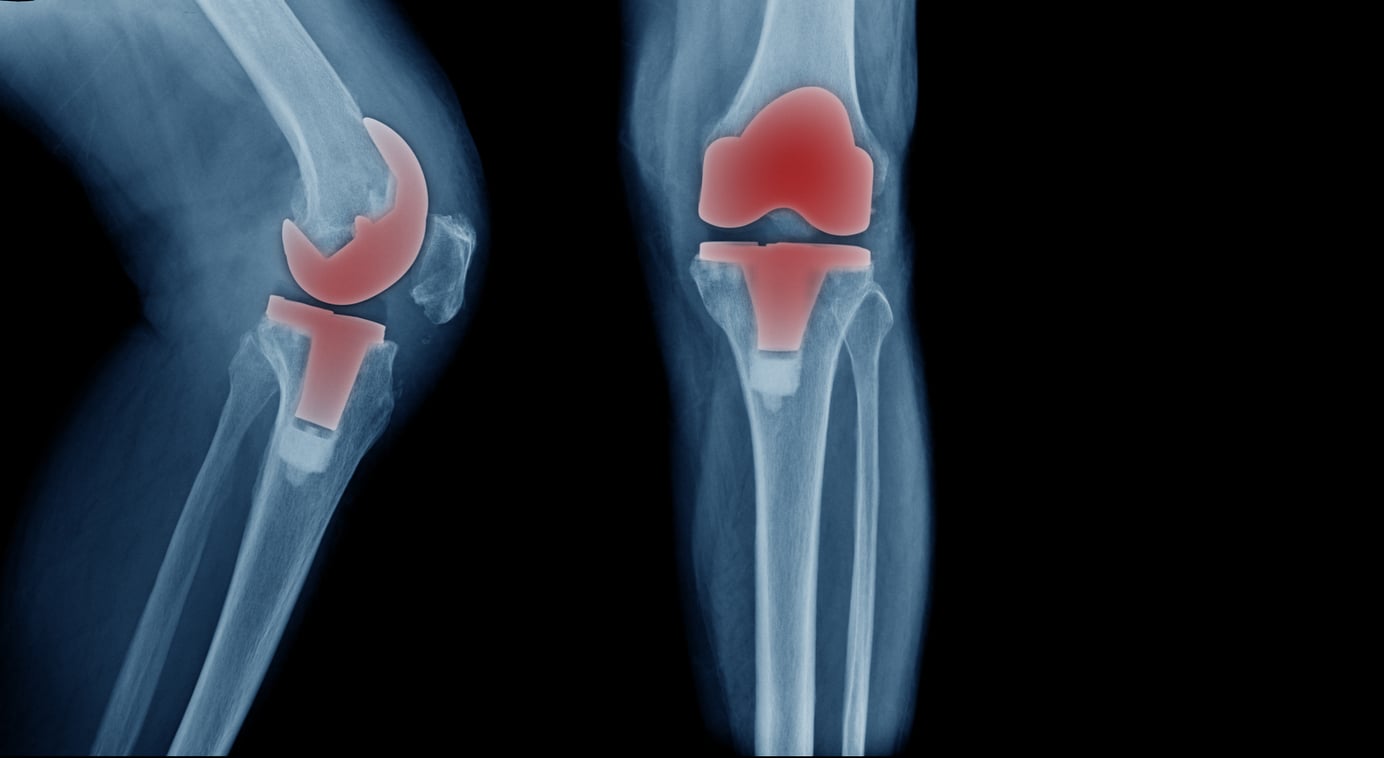

Stiffness in the knee and immobility that persist despite conservative treatments are significant indicators that you might need a knee replacement. Chronic stiffness can severely restrict your range of motion, making it difficult to perform everyday activities such as walking, standing, or bending your knee. This limitation often results from advanced arthritis or significant joint damage, where the cartilage has worn down, causing the bones to rub against each other. If physical therapy, medications, and other non-surgical treatments fail to improve the stiffness and you find that your mobility continues to deteriorate, it may be time to consider knee replacement surgery. This procedure can relieve pain, restore function, and significantly improve your quality of life, allowing you to return to a more active and comfortable lifestyle.

Bowing of the leg, or the appearance of your leg curving inward or outward, can be a strong indicator that you may need a knee replacement. This condition often results from severe wear and tear on the knee joint due to advanced arthritis, where the cartilage that cushions the bones has significantly degraded. This degradation leads to bone-on-bone contact, causing the leg to bow as the joint becomes misaligned. The bowing not only alters the leg's appearance but also affects your overall gait and posture, leading to further discomfort and pain. If conservative treatments like bracing, physical therapy, or medications fail to correct the misalignment or alleviate the pain, knee replacement surgery may be necessary to restore proper joint function and alignment. By addressing the root cause of the bowing, knee replacement can help you regain mobility, reduce pain, and improve your quality of life.

When nonsurgical treatments such as medications, physical therapy, or lifestyle modifications no longer effectively manage your knee pain and other symptoms, it may be a sign that you need a knee replacement. Persistent pain, swelling, and stiffness that do not improve with these conservative measures indicate that the underlying joint damage is severe and that the knee is no longer responding to less invasive treatments. This scenario is common in cases of advanced osteoarthritis or other degenerative joint conditions where the cartilage has worn away, leading to bone-on-bone contact and significant discomfort. If you're finding it increasingly difficult to carry out daily activities and maintain your quality of life despite trying various nonsurgical options, consulting with an orthopedic specialist can help determine if knee replacement surgery is the appropriate next step. This procedure can alleviate pain, restore function, and improve your overall well-being, allowing you to return to a more active and fulfilling lifestyle.